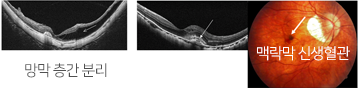

망막 층간 분리 및 맥락막 신생 혈관이 발생 할 수 있으며 이는

갑작스런 시력 저하를 유발합니다.

적절한 치료로 더 이상의 시력 저하를 막는 것이 최선의 치료

입니다.